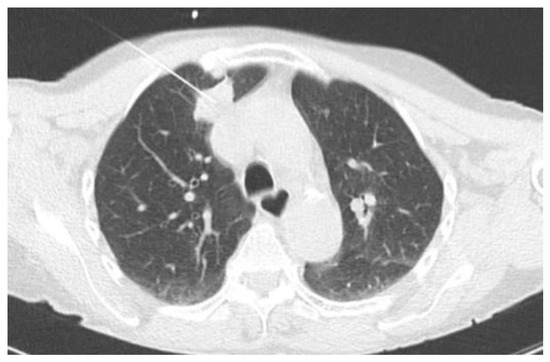

2.2.1. TIME 0: Lesion marking and SPECT Analysis